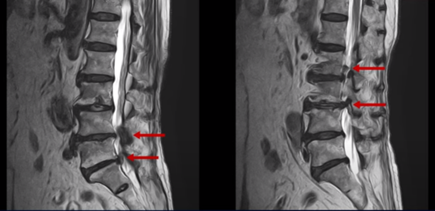

이분의 허리 MRI를 보면 여러 마디에 퇴행성 변화가 있습니다.

우선 5번 1번 마디를 보면 오른쪽으로 디스크도 밀려나와있고 또한 추간공도 좁아져 있는 것이 보입니다. 이걸 협착이라고 합니다.

1년 전부터의 오른쪽 다리 증상은 이 추간공이 좁아져서 생긴 추간공협착증 증상 때문인 것으로 보입니다.

또 위로 올라가서 2번 3번 관절을 보면 왼쪽으로 디스크가 파열되어 위로 밀려 올라가있고

3번 4번 마디를 보면 왼쪽으로 디스크가 많이 밀려나와 있습니다.